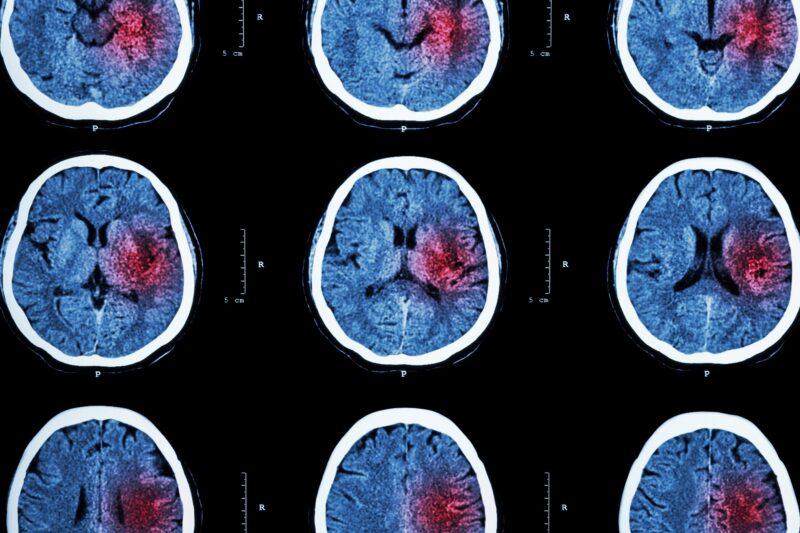

Brain Damage from Lack of Oxygen Stock Image M108/0774 Science How Much Lack Of Oxygen Causes Brain Damage It could cause serious, permanent brain. anoxic or hypoxic brain injury happens when your brain loses oxygen supply. Describe the evaluation of a patient with hypoxic brain injury. brain hypoxia happens when a person’s brain does not receive enough oxygen. This can occur when someone is drowning, choking, suffocating, or in cardiac arrest. Stroke, which occurs when blood. How Much Lack Of Oxygen Causes Brain Damage.